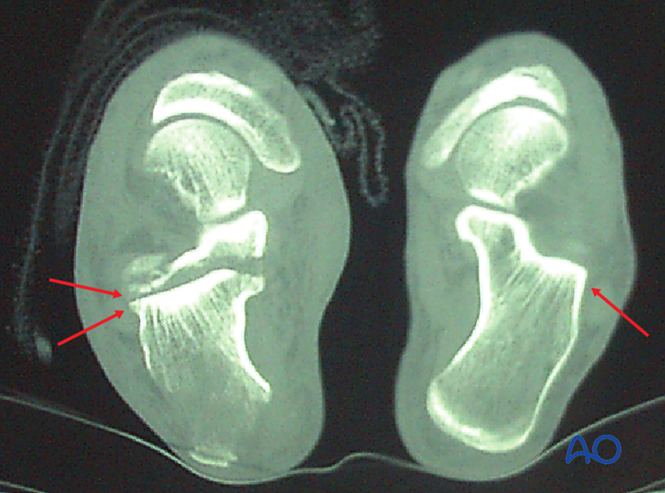

计算机断层扫描(Computed tomography, CT)

软组织条件允许时,CT可精确评估关节移位。图示正常足与鸟嘴样骨折患者的轴位CT,显示关节面"双线征",提示关节面劈裂。